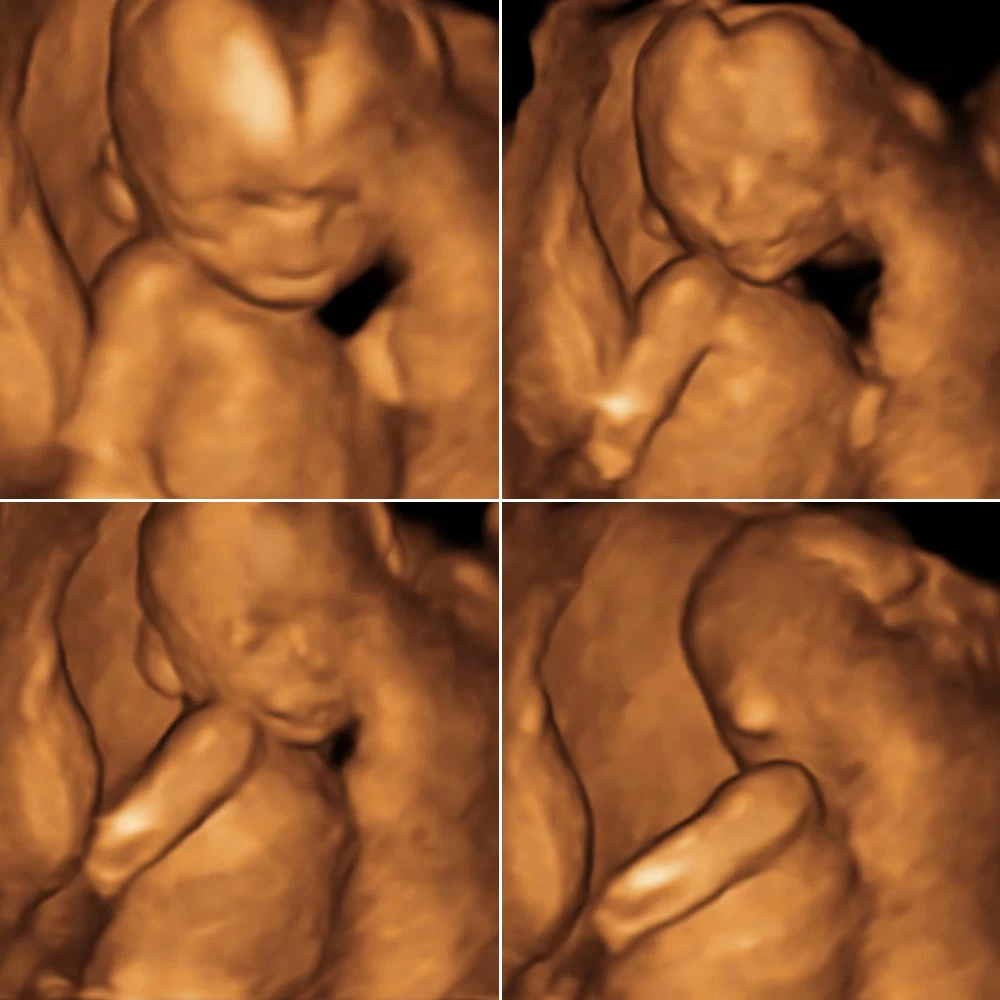

Плод начинает совершать активные движения, может сжимать пальцы. Головка опущена, подбородок тесно прижат к груди.

Продолжается развитие нервной системы. При прикосновении к стенкам матки ребенок совершает движения в ответ: поворачивает голову, сгибает или разгибает руки и ноги, отталкивается в сторону. Размеры плода еще очень малы, и женщина пока не может ощущать эти шевеления.

Плод свободно перемещается в полости матки: ложится вниз головой или ягодицами, поперек матки. Может играть пуповиной, отталкиваться руками и ногами от стенок матки.

Совершенствуется нервная система плода: головной мозг содержит уже все нервные клетки (нейроны) и имеет массу около 100 грамм. Ребенок начинает интересоваться своим телом: ощупывает свое лицо, руки, ноги, наклоняет голову, подносит пальцы ко рту.